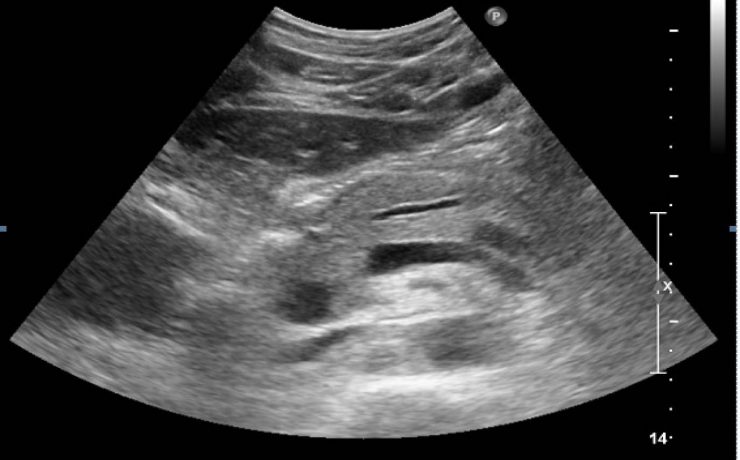

Correlación ultrasonográfica e histopatológica de los tumores de ovario

El cáncer de ovario, constituye el 2 % de las afecciones malignas de la mujer con una alta mortalidad, aproximadamente las dos terceras partes se presentan con lesiones muy avanzadas en el momento del examen imagenológico,1-4 trae por consecuencia una supervivencia menor de la paciente y un aumento del costo